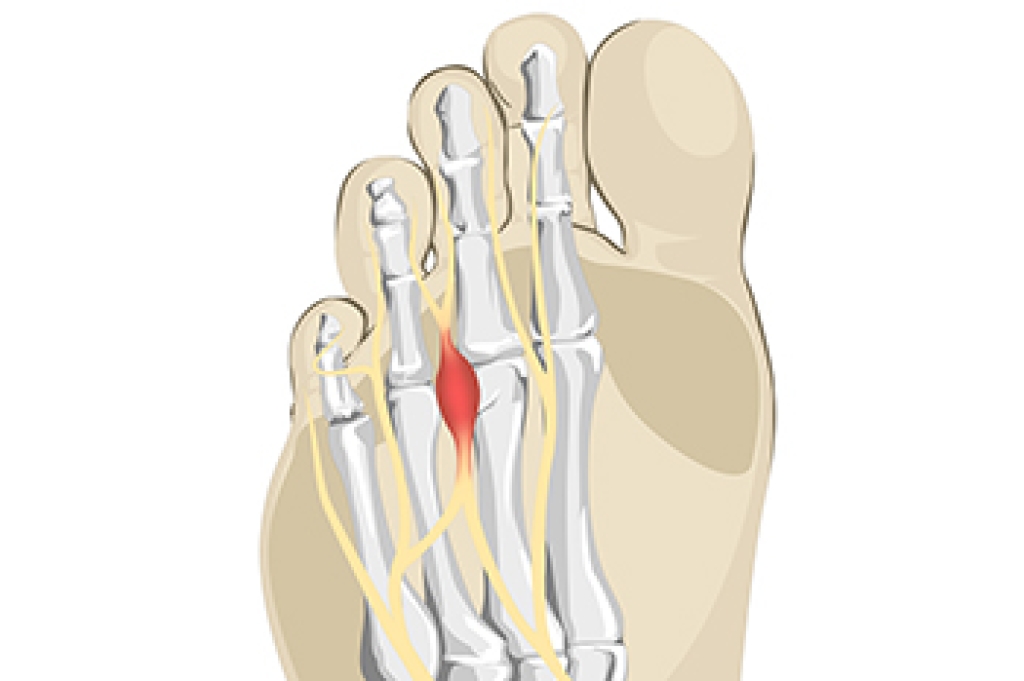

Spotting the Symptoms of Morton’s Neuroma

Morton’s neuroma is a nerve condition that often affects the ball of the foot, typically between the third and fourth toes. Common symptoms include sharp or burning foot pain, tingling, and numbness that may worsen with walking or wearing tight shoes. Many people describe the sensation as feeling like a pebble or small object is stuck inside the shoe. Causes include repeated pressure on the forefoot, improper footwear, and biomechanical foot problems. Risk factors include wearing high heels, intense physical activity, and foot deformities like bunions or flat feet. A podiatrist can diagnose this condition and recommend effective treatment. If you experience persistent foot discomfort, it is strongly suggested that you seek care from this type of doctor to find relief and prevent further complications.

Morton’s Neuroma

Morton's neuroma is a painful foot condition that commonly affects the areas between the second and third or third and fourth toe, although other areas of the foot are also susceptible. Morton’s neuroma is caused by an inflamed nerve in the foot that is being squeezed and aggravated by surrounding bones.

Morton’s neuroma is a very treatable condition. Orthotics and shoe inserts can often be used to alleviate the pain on the forefront of the feet. In more severe cases, corticosteroids can also be prescribed. In order to figure out the best treatment for your neuroma, it’s recommended to seek the care of a podiatrist who can diagnose your condition and provide different treatment options.